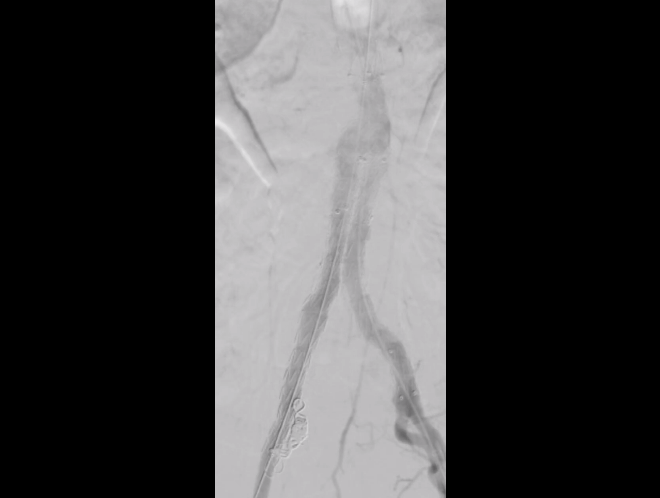

△术中造影

在血管外科赵海涛主任、必力格、乔栋嘉、周福兴3位医生及麻醉科医护人员配合下,历时3个小时,成功完成我院第一例腹主动脉瘤腔内隔绝术。术后患者恢复良好,可正常进食,并下床活动,获得满意疗效。